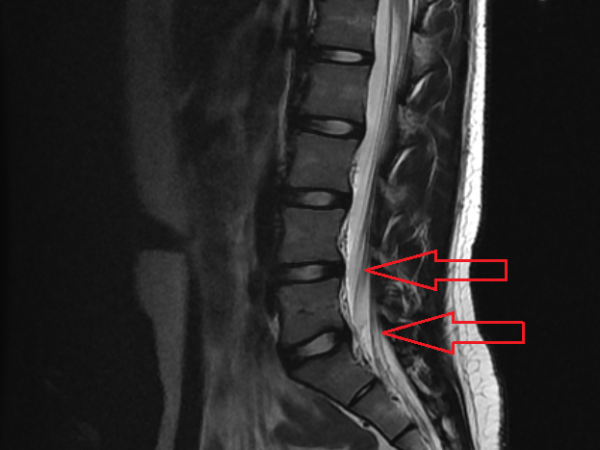

PHS효과?